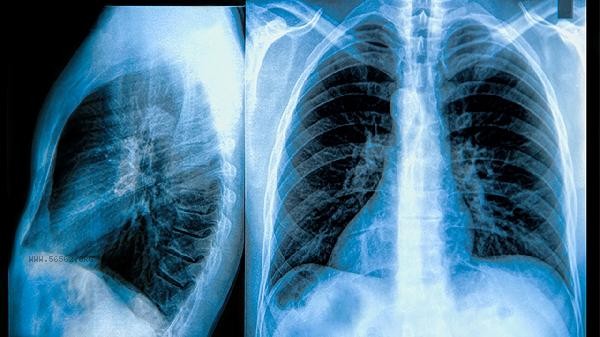

The TCM treatment of COPD mainly includes Chinese herbal decoction, acupuncture and moxibustion therapy, acupoint application, massage, Qigong conditioning, etc. Chronic obstructive pulmonary disease (COPD) belongs to the category of lung distension and wheezing in traditional Chinese medicine, and is often related to dysfunction of the lungs, spleen, and kidneys. It is recommended that patients receive diagnosis and treatment under the guidance of professional TCM practitioners.